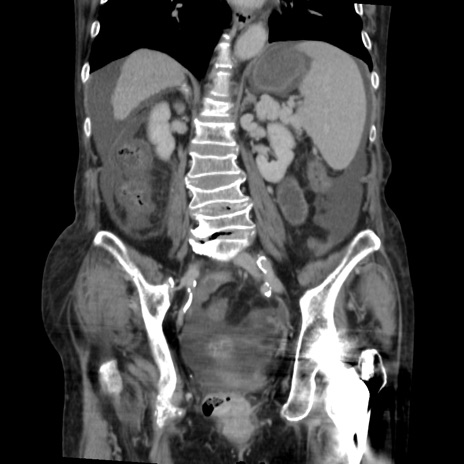

症例31(冠状断像)

【症例】80歳代 女性

【主訴】腹部膨満感

【現病歴】他院にて肝硬変にてフォロー中。1週間前から便秘、腹部膨満感、臍部腫瘤あり受診となる。

【既往歴】肝硬変

【身体所見】腹部膨隆あり、皮膚変化なし、疼痛なし。

【データ】WBC 4600、CRP 0.25